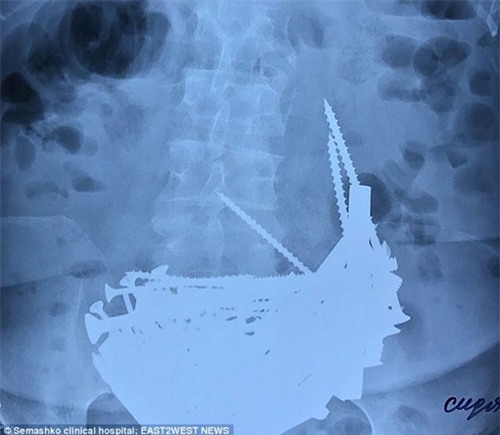

Bà nhập viện do bị sốt nhưng sau khi kiểm tra phim chụp X-quang, các bác sĩ sửng sốt khi phát hiện ra nguyên nhân của hiện tượng này. Có tới hơn 152 vật thể lạ trong bụng của bà cụ về hưu này.

Các bác sĩ đã tiến hành phẫu thuật và lấy ra rất nhiều đinh dài, ốc vít, bu lông, chốt cửa... có cái dài đến hơn 15cm. Thậm chí còn có cả một chiếc vòng bạc.

Bà cụ U80 này nói với bác sĩ là bà bị thiếu máu do đó bà tin rằng ăn các vật bằng kim loại sẽ giúp bổ sung chất sắt, cải thiện tình trạng này của mình. Bà đã bắt đầu nuốt đinh vít và các vật bằng kim loại bắt đầu từ 14 năm trước.